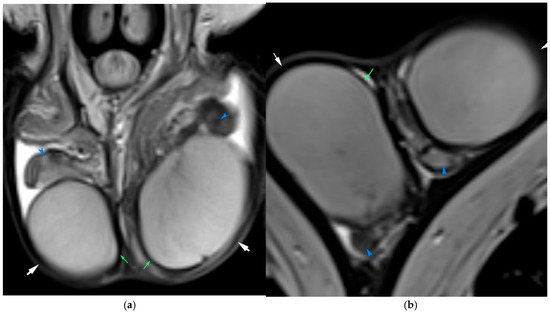

Background: Magnetic resonance imaging (MRI) plays an increasingly important role in the evaluation of scrotal and penile disorders, complementing ultrasonography in cases where findings are equivocal or complex. With its superior soft-tissue contrast, multiplanar capability, and advanced functional sequences, MRI provides unparalleled anatomic and tissue characterization across a wide range of male genital pathologies. Summary: This review summarizes current clinical applications of MRI in scrotal and penile imaging and discusses its diagnostic value, protocol optimization, and interpretive features. In scrotal pathology, MRI accurately differentiates torsion, trauma, infection, and neoplasms, aiding in the distinction between benign and malignant testicular lesions and supporting testis-sparing management. Quantitative diffusion and perfusion metrics further refine lesion characterization. In andrology, MRI biomarkers such as apparent diffusion coefficient (ADC), magnetization transfer ratio (MTR), and proton spectroscopy serve as promising non-invasive indicators of spermatogenic activity in male infertility. In penile imaging, MRI enables precise local staging of carcinoma, assessment of plaque morphology and activity in Peyronie’s disease, evaluation of tissue viability in priapism, and detection of prosthesis-related complications. Conclusions: MRI has become an essential problem-solving tool in the assessment of scrotal and penile diseases, enhancing diagnostic confidence and surgical planning. Future directions include protocol standardization, quantitative parameter validation, and the integration of radiomics and artificial intelligence to improve reproducibility and clinical impact. Full article